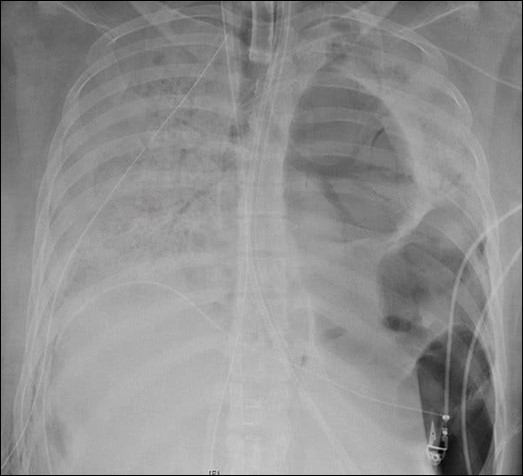

A 20-years-female received a double lung transplant following end-stage lung disease (Figure 1 & Figure 2) by COVID-19 at Northwestern Medicine in Chicago12. She was the first COVID-19 lung transplant case for the United States of America12. COVID-19 pandemic which started from China outspread to Europe and the United States of America, reached to South Asian countries at last. Thus this provides us with an opportunity to act accordingly those already affected countries have acted to control this pandemic before it is out of control. In Nepal there are many cardiothoracic and vascular surgeons capable enough for lung transplantation, however its legal system lag behind the clinical system. The first law enacted to regulate human organ transplantation in Nepal with title "The Human Body Organ Transplantation (Regulation and Prohibition) Act, 2055 (1998) provides provision for only Kidney transplantation as solid organ transplantation13. Recent modification in the existing law in the form of Human Body Organ Transplantation (Regulation and Prohibition) Act 207214 and Human Body Organ Transplantation (Regulation and Prohibition) legislation 207315 has provided provision for Liver transplantation too but not for other solid organ transplantation like lung. Keeping in view of urgent need of lung transplantation to save the life of end-stage COVID-19 cases as shown in the cases done in China, Europe and the United States of America, this research has been done as a small step towards the preparedness for ongoing COVID-19 pandemic with an aim to see the perception of health care professionals of tertiary care centre of eastern Nepal regarding the legal aspects of lung transplantation.

Figure 1.An X-ray of the patient’s lungs before surgery. Northwestern Medicine